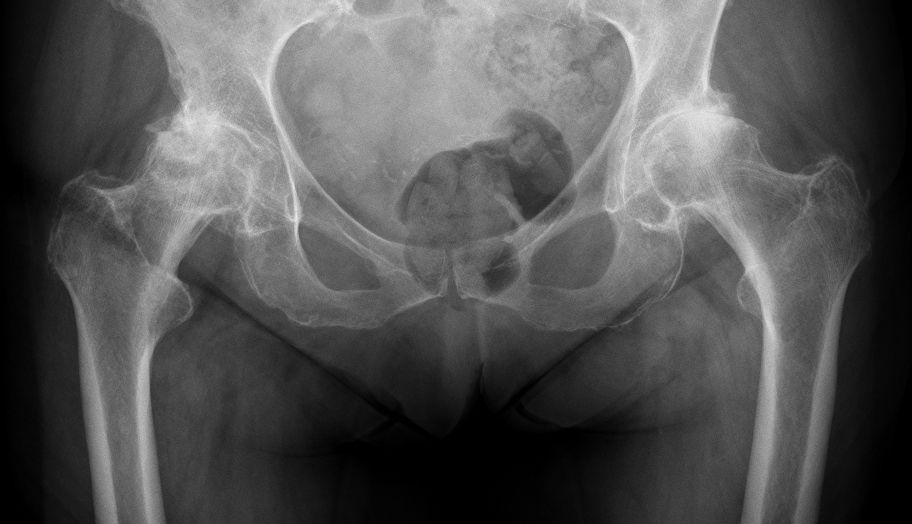

This article will explain how we have tried to achieve each of these goals of a personalized hip replacement. Whilst acknowledging that there may be multiple successful ways and that options may evolve, our current preference is for a large diameter head (LDH) THA. We define an LDH bearing as femoral head >36mm and/or a cup–head diameter difference ≤12mm (e.g. 46mm cup with a 36mm head (Fig. 1). LDH THA is mainly available in two designs: ceramic-on-Ceramic (CoC) LDH THA with a monobloc acetabular cup, or dual mobility (DM) LDH THA.

Precise biomechanical reconstruction of the hip is essential for the success of this procedure. Better clinical function and abductor strength can be achieved from optimal femoral offset and restoration of leg length. Otherwise, failure to restore the normal anatomy during THA has been associated with a higher rate of dislocation, muscle weakness, limping, leg-length discrepancy, impingement, and early loosening of the implant (Fig. 4).